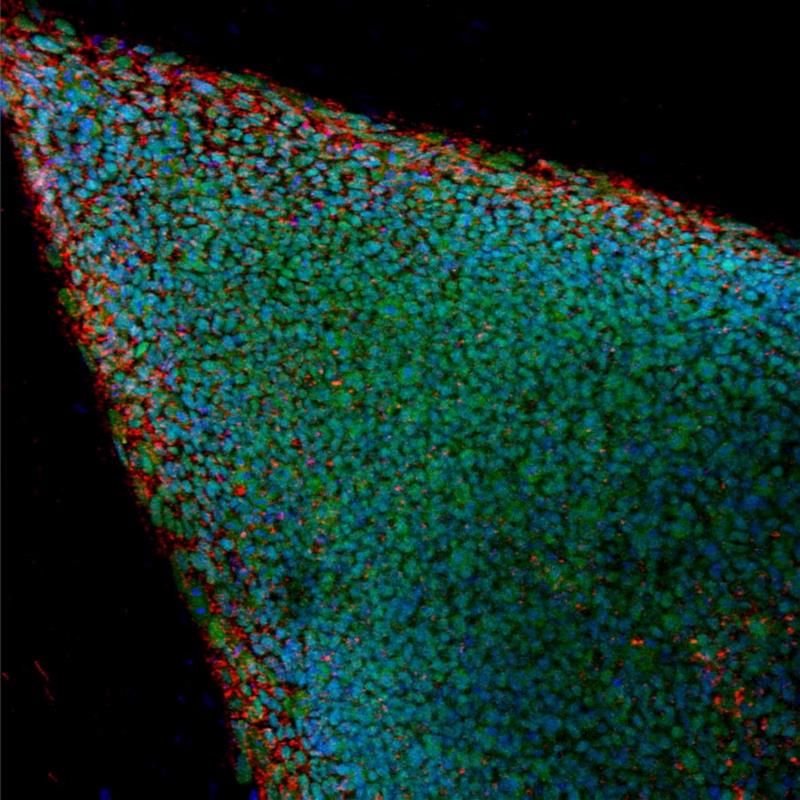

6489291wTokio, 22 jul (EFE).- Un equipo de la Universidad de Gifu (centro de Japón) ha comenzado a crear un banco de células madre pluripotentes inducidas (iPS) obtenidas a partir de pulpa dental procedente de muelas del juicio que han sido extraídas, informó hoy el diario Nikkei.

Este banco genético servirá como fuente de células iPS humanas para investigación clínica en medicina regenerativa.

El proyecto consiste en analizar las muelas y, de aquellas cuyo material genético sea inmunológicamente compatible con amplias partes de la población japonesa, obtener iPS para realizar cultivos y almacenarlos.